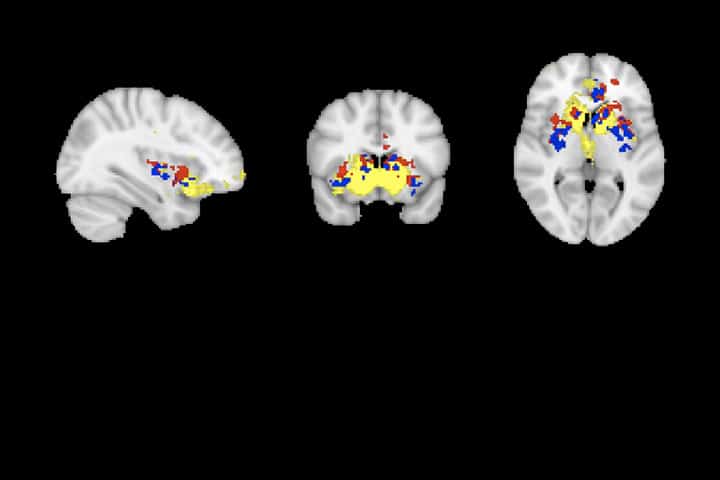

Short humorous internet films are watched every day by most young adults, and can help to reduce and distract from augmented stress, such as during the COVID-19 global pandemic. In a unique collaboration between researchers from SANPSY, INCIA and IMN, all teams part of Bordeaux Neurocampus, we show that brain activity is increased in the brain reward network (caudate nucleus, anterior cingulate gyrus, putamen and insula) in a group of 20 young adult insomnia patients presented with short humorous films.

This increase is related to hyperarousal levels, a typical feature of insomnia. Interestingly, humor ratings did not differ between those with insomnia and a group of 20 age- and gender-matched participants without insomnia: both groups thus rated the films as equally humorous. Brain activity patterns related to humorous films in insomnia thus show a similar pattern as those found after experimental sleep deprivation, but are less similar to effects typically found in depression, which is a comorbid symptom of insomnia. Future studies could show if, by activating the reward network, humorous film viewing could have sleep-enhancing effects in insomnia.